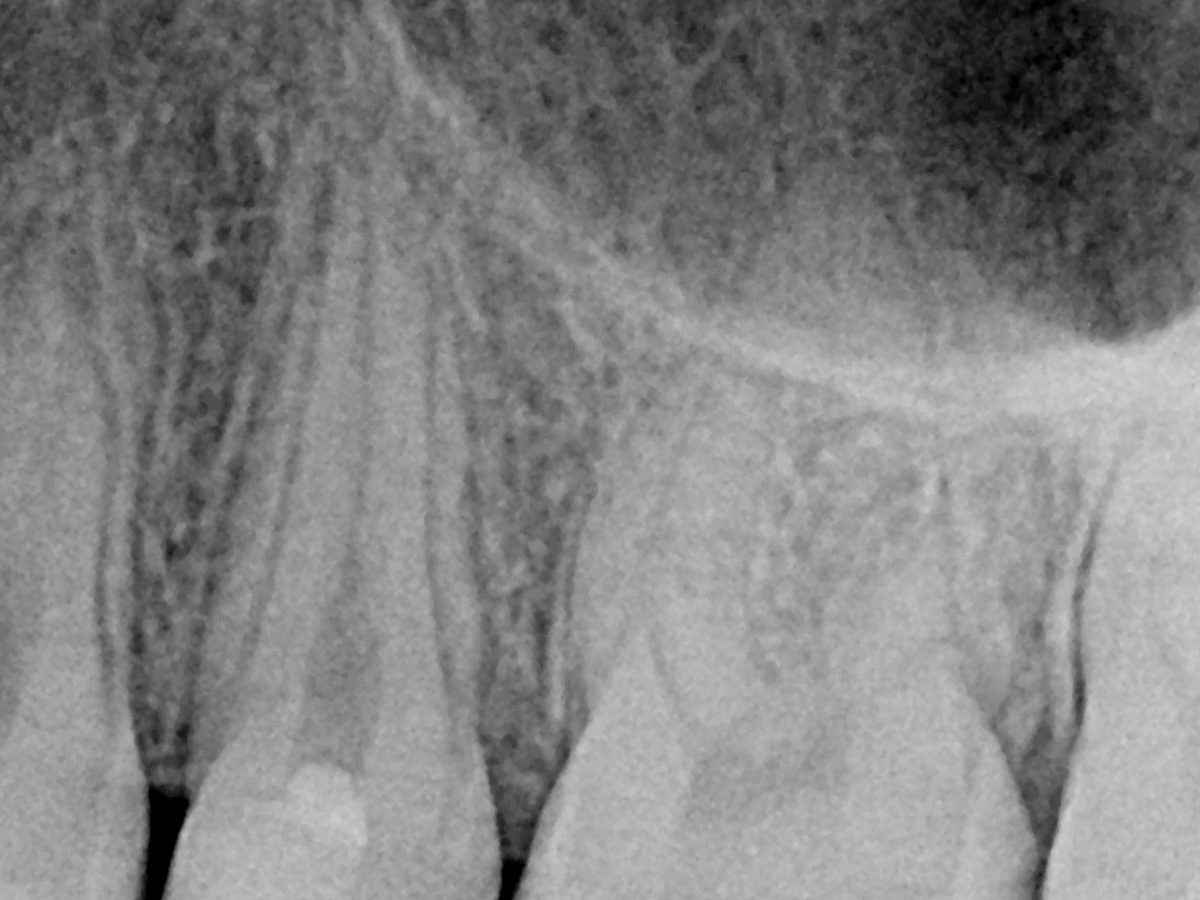

Abbildung 2

Ausgangssituation.